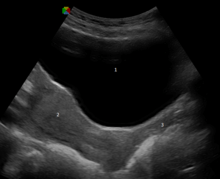

An ultrasound showing the urinary bladder (1), uterus (2), and vagina (3)

The vagina is self-cleansing and therefore usually does not need special hygiene. Doctors generally discourage the practice of douching for maintaining vulvovaginal health.[62] Since a healthy vagina is colonized by a mutually symbiotic flora of microorganisms that protect its host from disease-causing microbes, any attempt to upset this balance may cause many undesirable outcomes, including but not limited to abnormal discharge and yeast infection.[62]